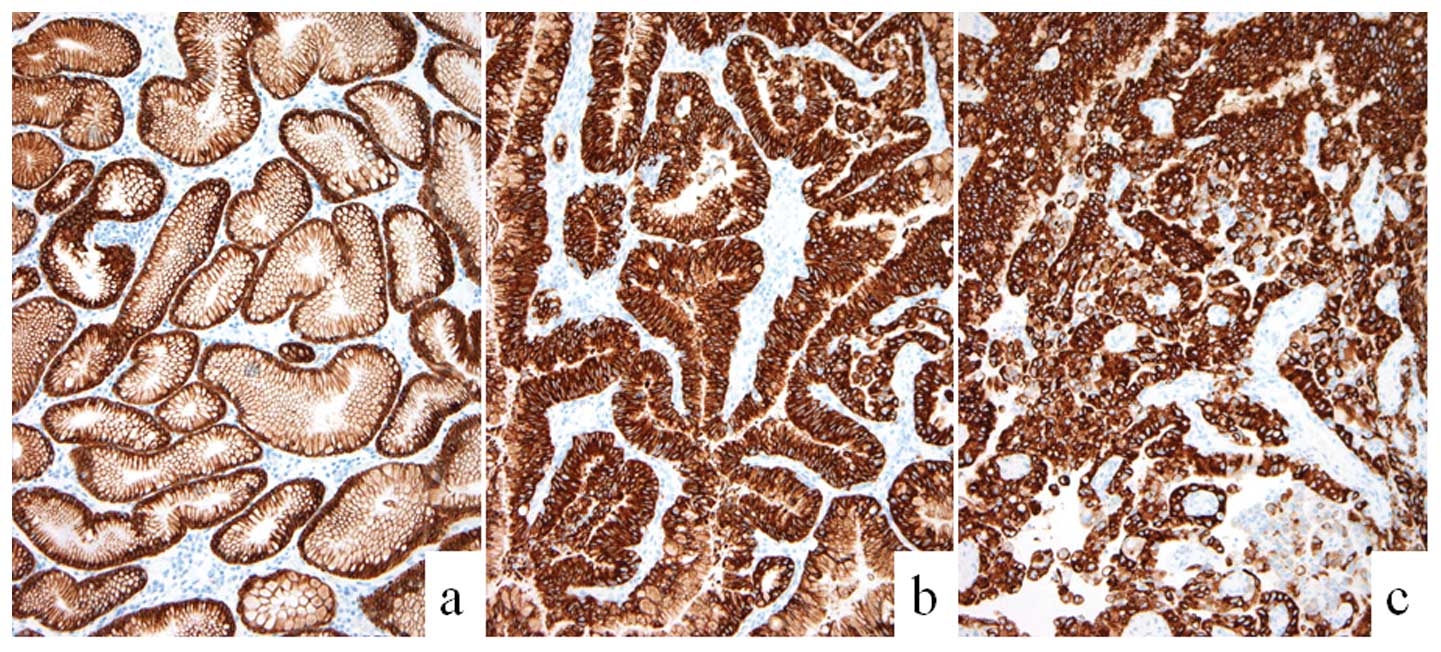

The present immunohistochemical study found that

MUC5AC was immunopositive in the hyperplastic, dysplastic and

carcinoma regions of the polyps; while this marker was detected in

the hyperplastic and dysplastic areas only, but not in the

carcinomatous component, in one case. These observations suggested

that the lesions were mostly of the gastric mucin type (Fig. 3). Furthermore, MUC2 expression was

not observed in any of the specimens and goblet cells were also

undetected, thus, the lesions were unlikely to be of the intestinal

mucin type. Immunoreactivity for MUC1 in three cases and MUC6 in

case (Fig. 4). The tight junction

factor, claudin-3, was completely absent in the hyperplasia area,

but was immunopositive in the dysplastic and carcinomatous

components. By contrast, expression of claudin-4 was observed in

the dysplastic and carcinomatous component of all cases (Fig. 5). In addition, expression of

claudin-18 was observed in the hyperplastic, dysplastic and cancer

components of all cases. The frequency of cells with abnormal